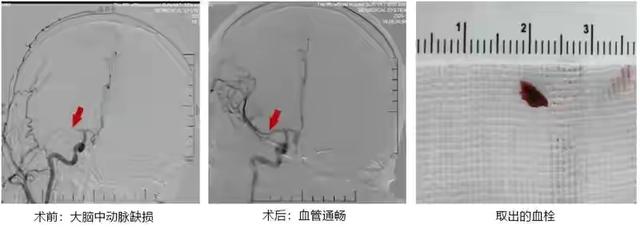

后来小张被送往当地医院急诊科,医院当即给做了紧急抢救,才得以脱离危险。但是情况很不乐观,通过CT检查下来发现小张的大脑中动脉内有很明显的血栓。这是引起脑梗塞的最直接原因,血栓很大,单凭药物是很难解决,只能靠手术植入支架取出血栓。好在这一切发现得及时,小张也很顺利地取出了血栓,病情也得到了缓解。